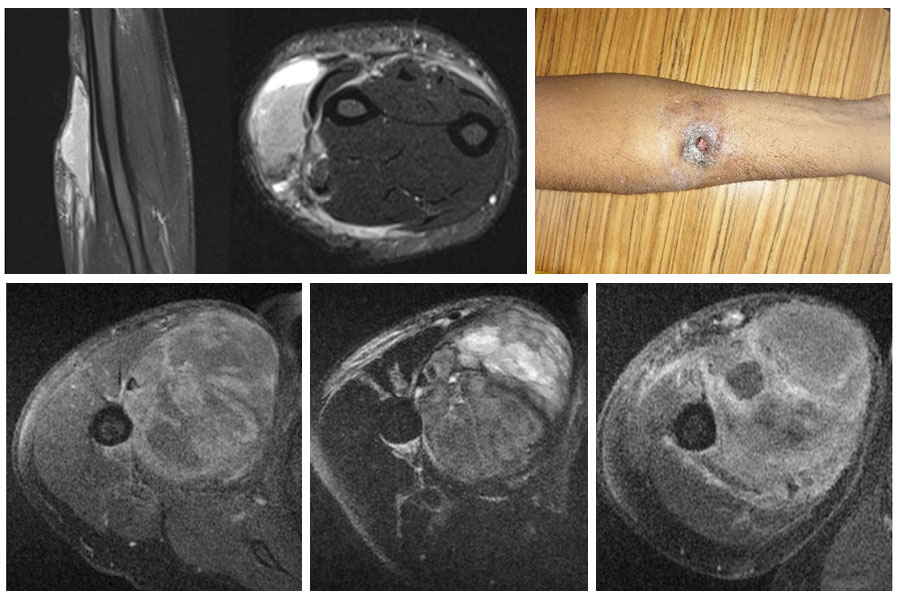

Эпителиоидную саркому можно разделить на две основные группы. Дистальный тип локализуется под кожей в нижних отделах колена и локтя в более молодом возрасте. Через некоторое время (2-3 месяца) они могут прорвать кожу и изъязвиться (12%). При проксимальном типе они располагаются вокруг плеча и туловища в верхней конечности и вокруг бедра и паха в нижней конечности. Они расположены более глубоко и имеют больший размер.

Границы образования могут быть нечеткими на Магни́тно-резона́нсной томогра́фии и могут выглядеть как множественные очаги. Соседние сосуды, нервы и кости могут быть окружены опухолью. Внутри опухоли может наблюдаться кальцификация (оссификация). Могут наблюдаться кровоизлияния и некроз, особенно в больших опухолях.